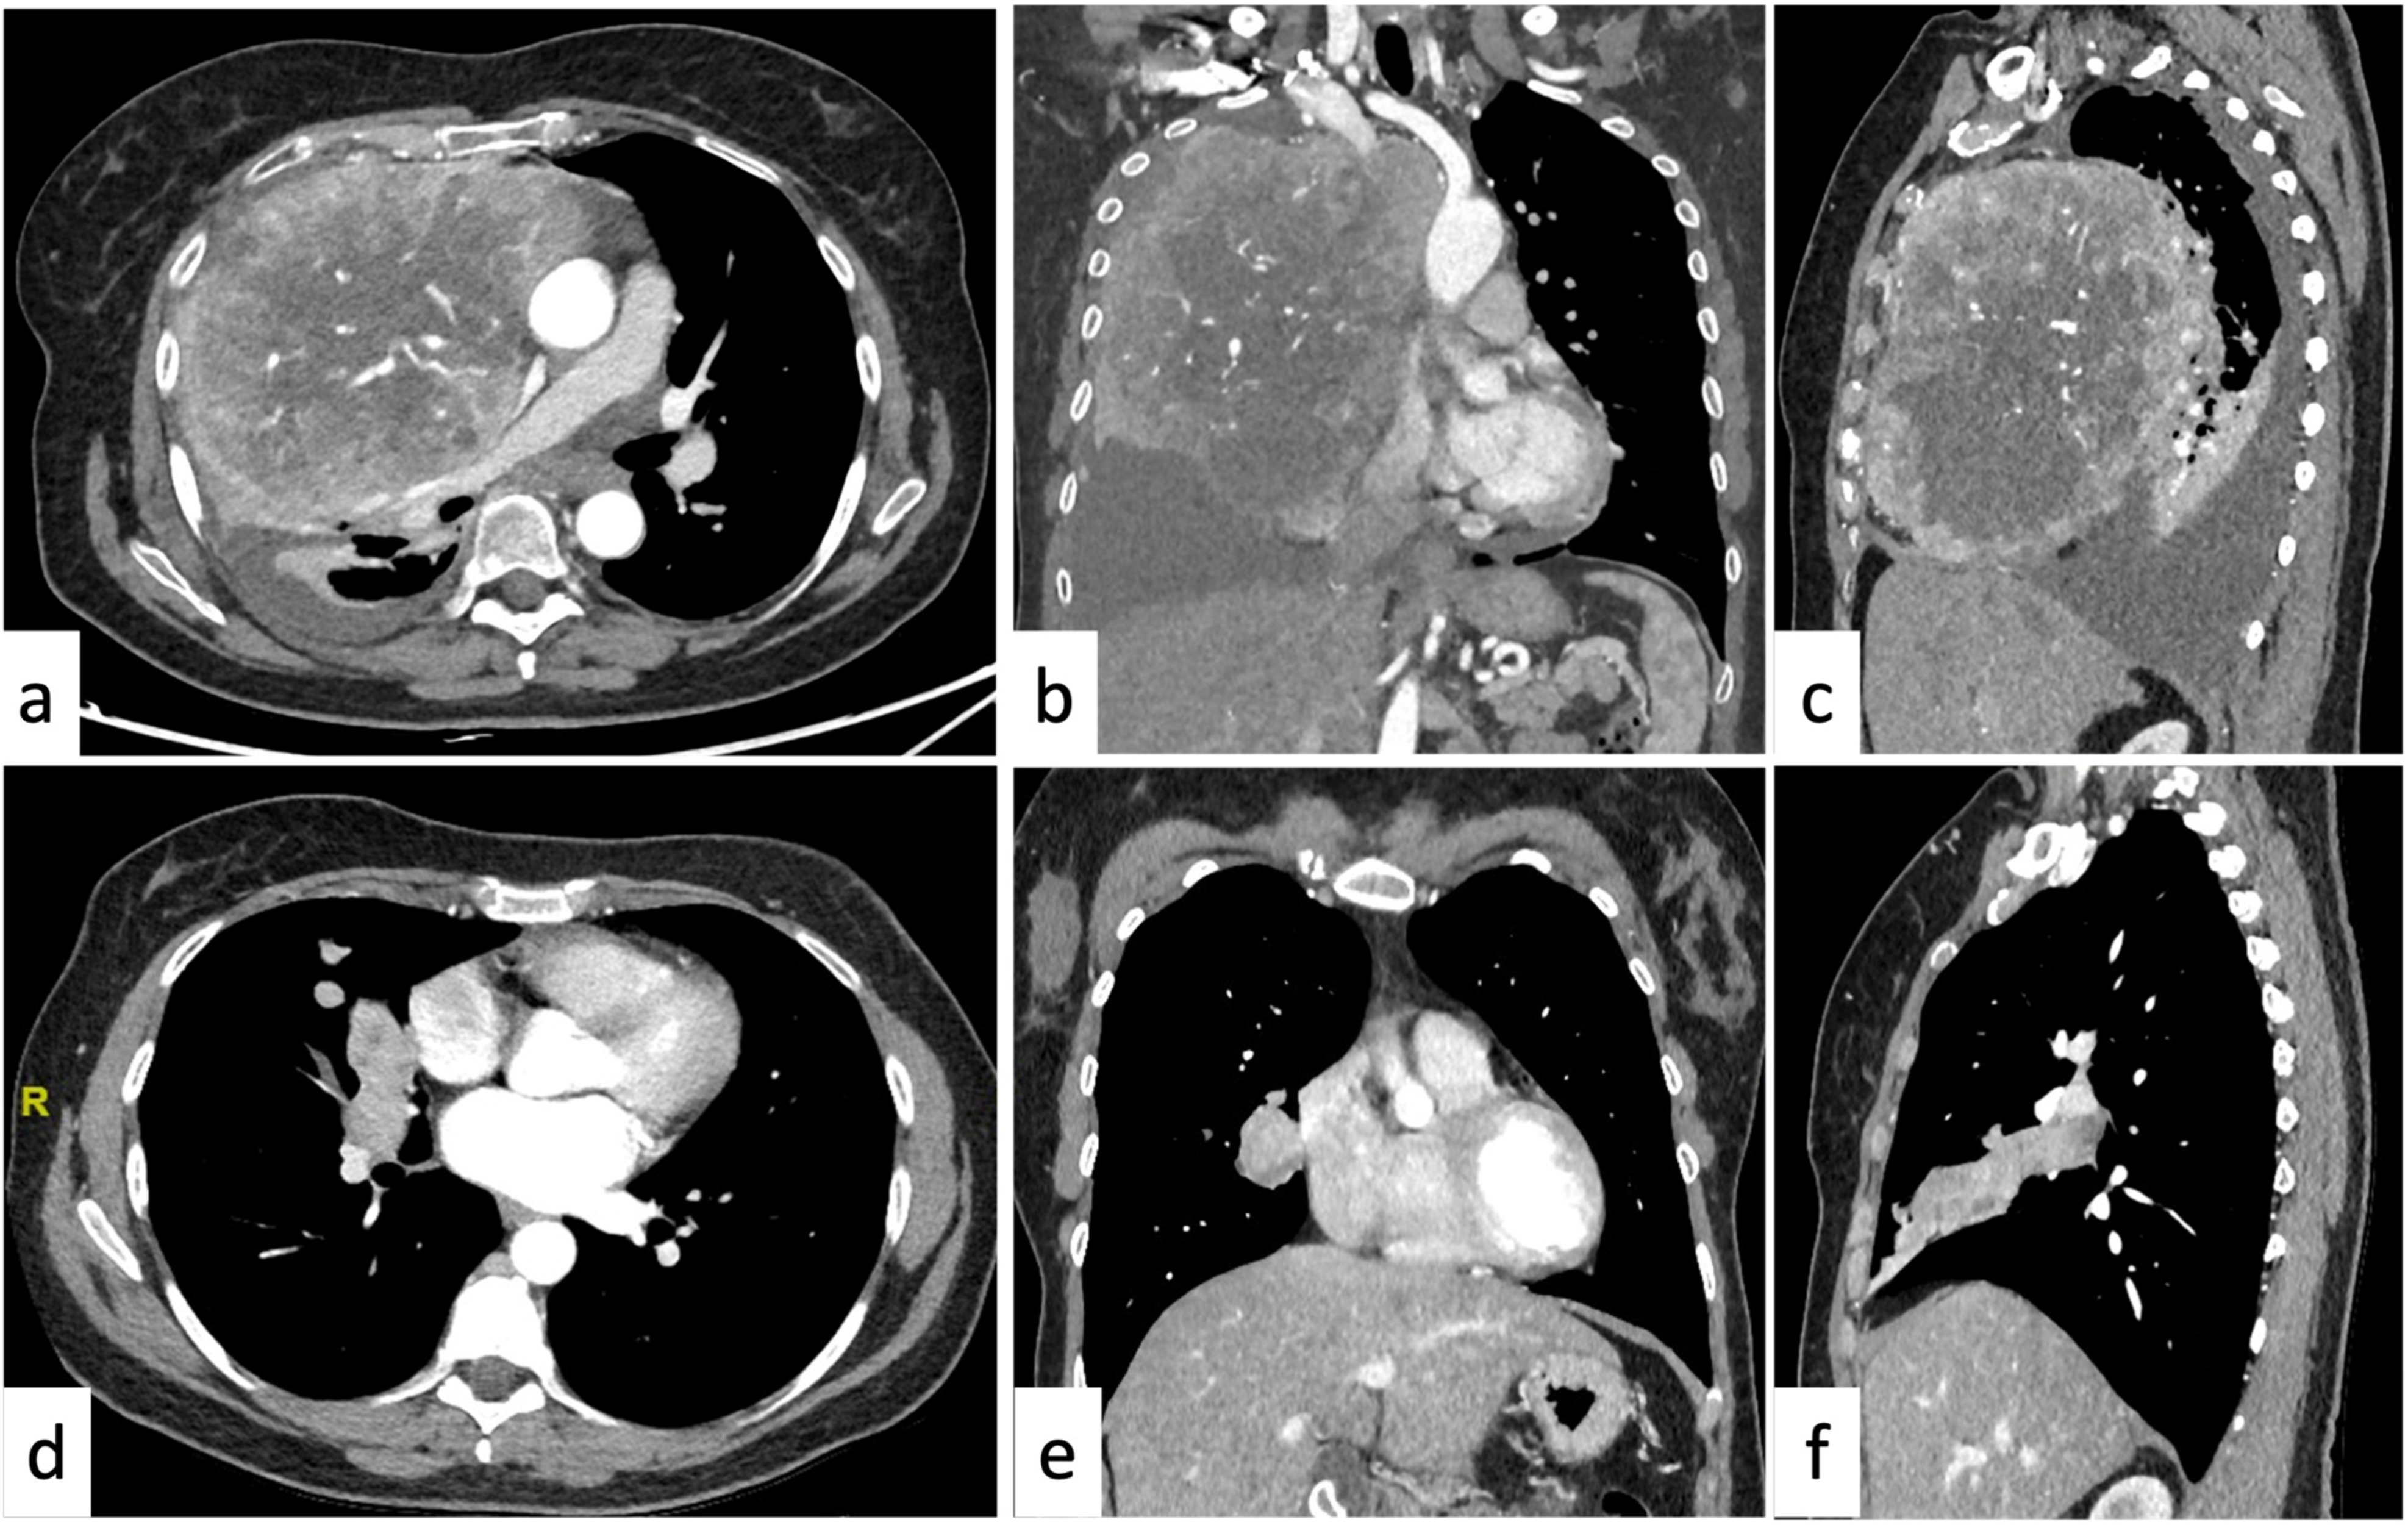

2.4. More than One Mediastinal Compartment

| >1 compartment (11.2%) | Liposarcoma Lipomatosis | Lymphangioma | Lymphadenopathy Lung cancer |